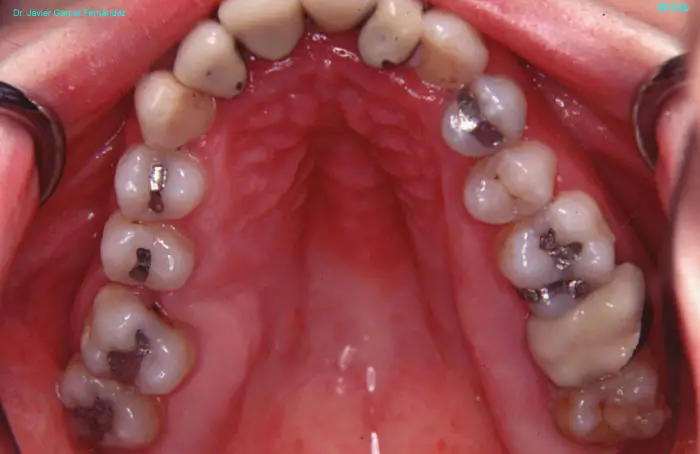

Atlas of Surgical Techniques in Periodontics. Chapter III. Atlas de Técnicas Quirúrgicas en Periodoncia